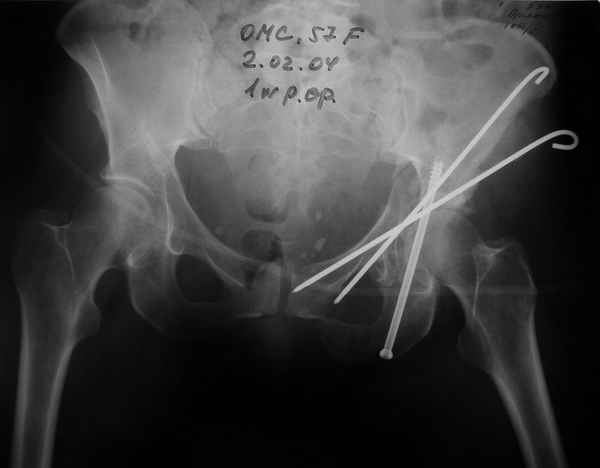

02.02.04

Откровенно говоря, репозиция оказалась очень непростым делом, несмотря на то, что при расширенном илео-феморальном доступе все переломы как на картинке.

Сначала пытался отрепонировать смещенную заднюю колонну, но ничего из этого не получалось пока не репонировал фрагмент крыла подвздошной кости, который клином входил между отломками тела илии и задней колонной дистанция-то всего каких-то 3-5 мм, но чтобы сложить этот puzzle пришлось попотеть, я уже и дистракционные щипцы и бедренный дистрактор крутил, в конце концов все состоялось, а передняя колонна уже саморепонировалась, мне оставалось только компрессирующие винты завинтить

Приблизительно так и сделал